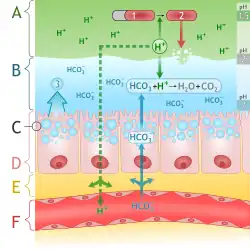

The mucus produced by these cells is extremely important, as it prevents the stomach from digesting itself.[5] Parietal cells produce potent hydrochloric acid, which damages cells. Gastric chief cells produce pepsinogen, which is activated by the acid to form pepsin. Pepsin is a protease that can digest and damage stomach cells. To prevent these disastrous effects, mucus and bicarbonate ions (HCO3−) are secreted by the foveolar cells.

The mucus allows the acid at pH above 4 to penetrate lining, but below pH 4 (i.e. when acid is more concentrated) the acid cannot penetrate the mucus. This is called viscous fingering.[6] Thus the foveolar cells can pump out a lot of acid, but acid once in the lumen of the stomach is prevented from returning.